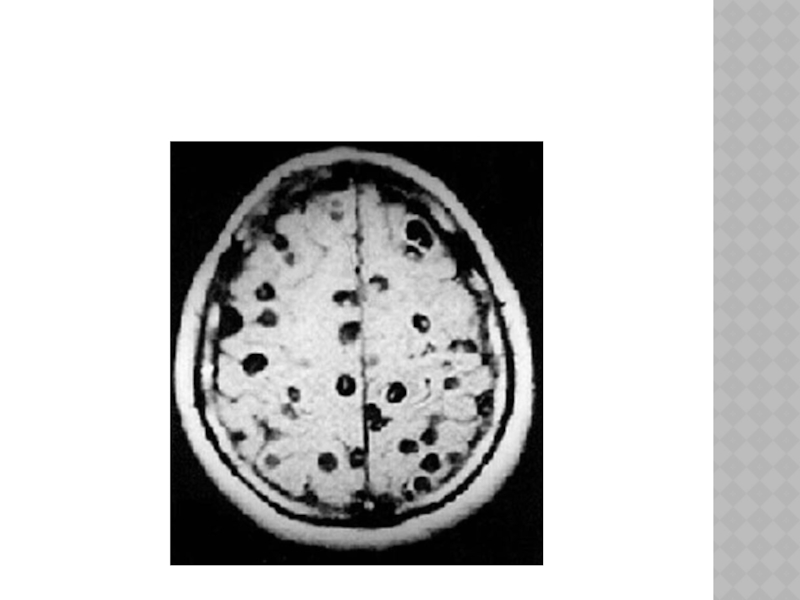

Слайд 137ЦИСТИЦЕРКОЗ ГОЛОВНОГО МОЗГА

-три

основные формы заболевания: 1).поражение больших полушарий(нарушения психики, мультифокальные эпилептические припадки, очаговые симптомамы, головные боли оболочечного характера), 2).поражение желудочковой системы(цистицеркоз желудочков мозга чаще бывает одиночным и локализуется в IV желудочке мозга, внутричерепная гипертензия, гидроцефалия боковых и III желудочков), 3).поражение основания мозга.